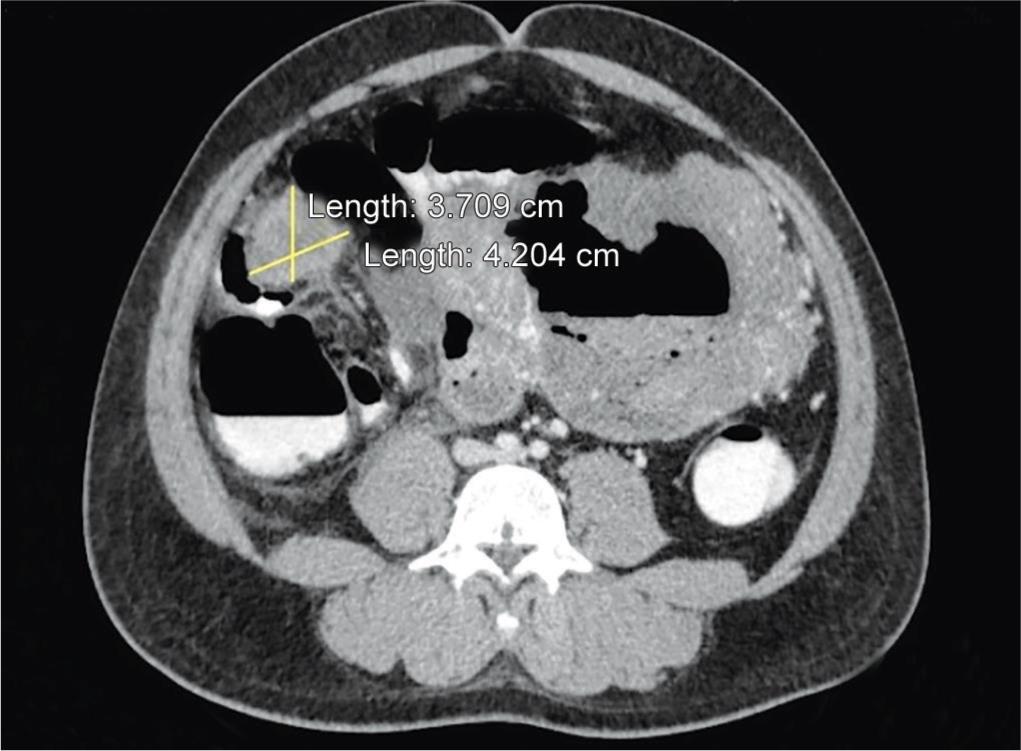

Multiple heterogeneously enhancing nodular omental and mesenteric deposits were seen, the largest of them in the right lumbar region with central areas of necrosis (Fig. 6).

Fig. 6: CECT also reveals multiple heterogeneously enhancing nodular omental and mesenteric deposits, with central areas of necrosis